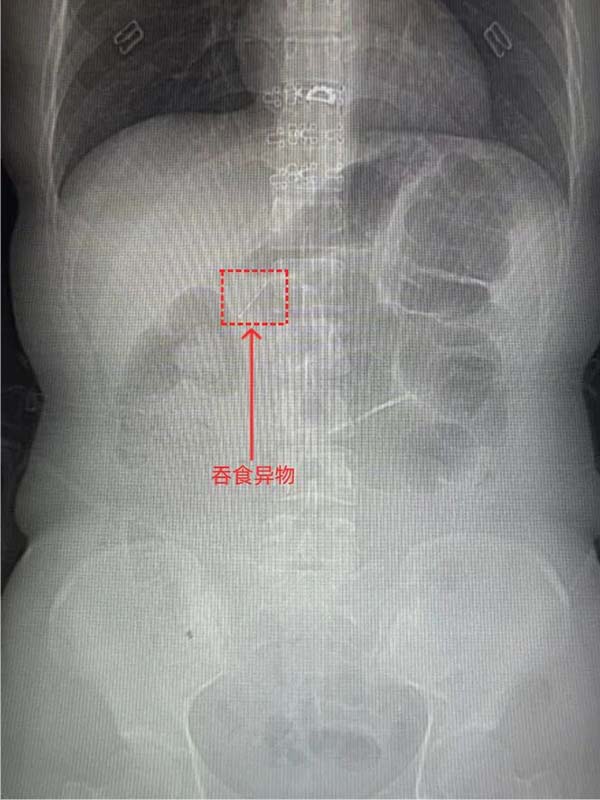

患者付某,女性,27岁,因“不慎吞食异物40分钟”于2025年12月23日18:04至中国中医科学院望京医院急诊外科就诊。患者无明显胸痛、腹痛、咽痛等不适。上腹、下腹、盆腔CT平扫:胃窦腔内细条形金属样高密度影,结合病史,考虑异物可能性大。与患者及家属充分沟通病情、交代内镜操作相关风险并获知情同意后,消化科牛然副主任医师带领内镜团队迅速为患者施行内镜下消化道异物取出术。镜下所见:进镜至十二指肠水平段时,于肠腔内探及一枚长约2厘米的金属细钉。该异物位置较深、形态细长,有坎顿、出血或穿孔的风险。幸运的是异物钳配合透明帽取出,过程顺利,所经过消化道粘膜观察无破损及划伤,患者无不适症状。

CT图